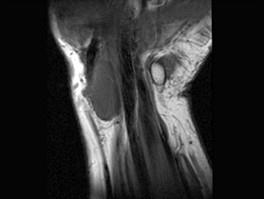

问题 男,69岁,腕部肿块1年,结合 图像,最可能的诊断是 ( )

选项 A、肌内脂肪瘤 B、未见异常 C、腕部腱鞘脓肿 D、腱鞘巨细胞瘤 E、腕部腱鞘囊肿

答案 E